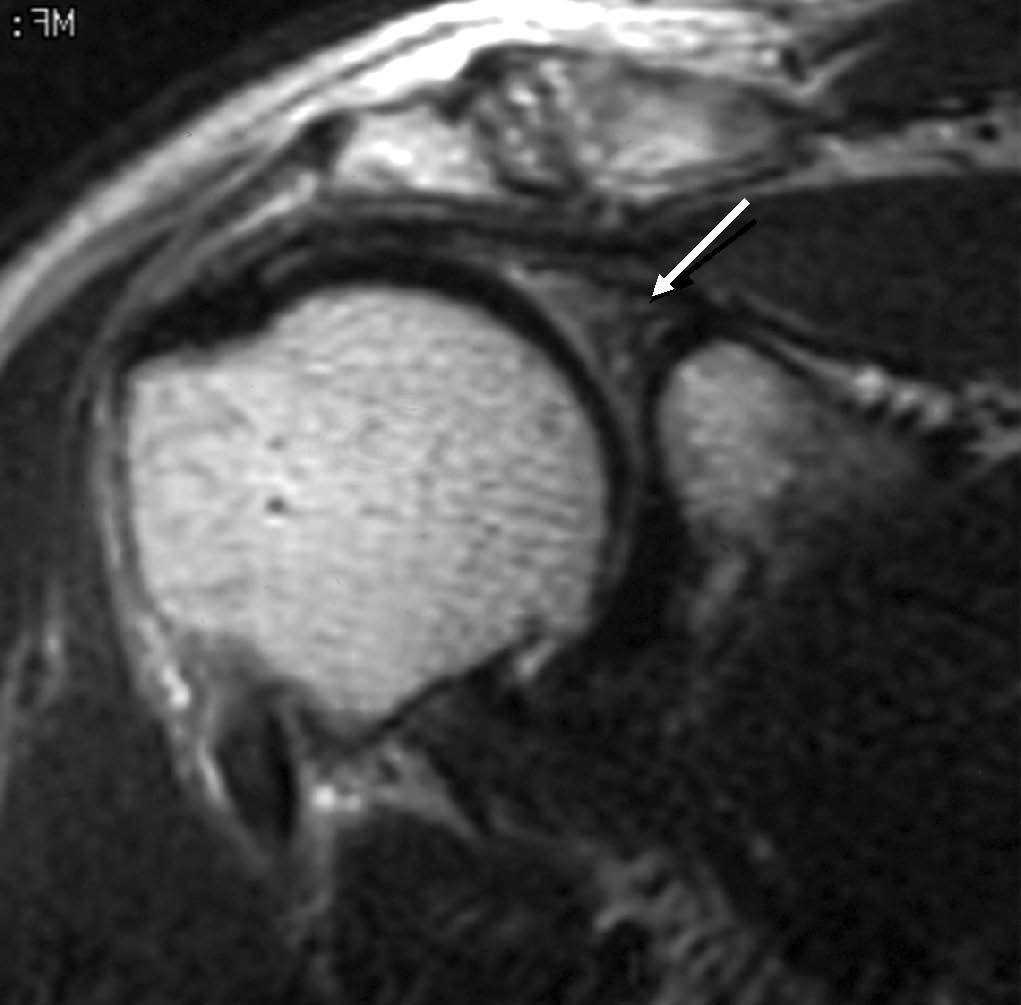

Lesión de Bankart

La lesión de Bankart se produce durante una dislocación anterior e inferior de la cabeza humeral, con impactación de la misma contra el borde anteroinferior de la glenoides, causando un arrancamiento del LG con rotura capsuloperióstica. Al mismo tiempo, se produce frecuentemente una fractura por impactación de la cabeza humeral (lesión de Hill Sachs) (fig. 9). En ocasiones, dicha lesión se acompaña de una fractura del borde anterior e inferior de la glenoides (Bankart óseo).

Fig. 9.--Lesión de Bankard y Hill-Sachs. Artrorresonancia axial T1, donde se observa un desprendimiento completo del labio glenoideo (flecha larga en A) con una rotura capsuloperióstica (cabezas de flecha en A). Nótese la fractura por compresión del margen posterosuperior de la cabeza humeral, representando una lesión de Hill-Sachs (flechas en B).